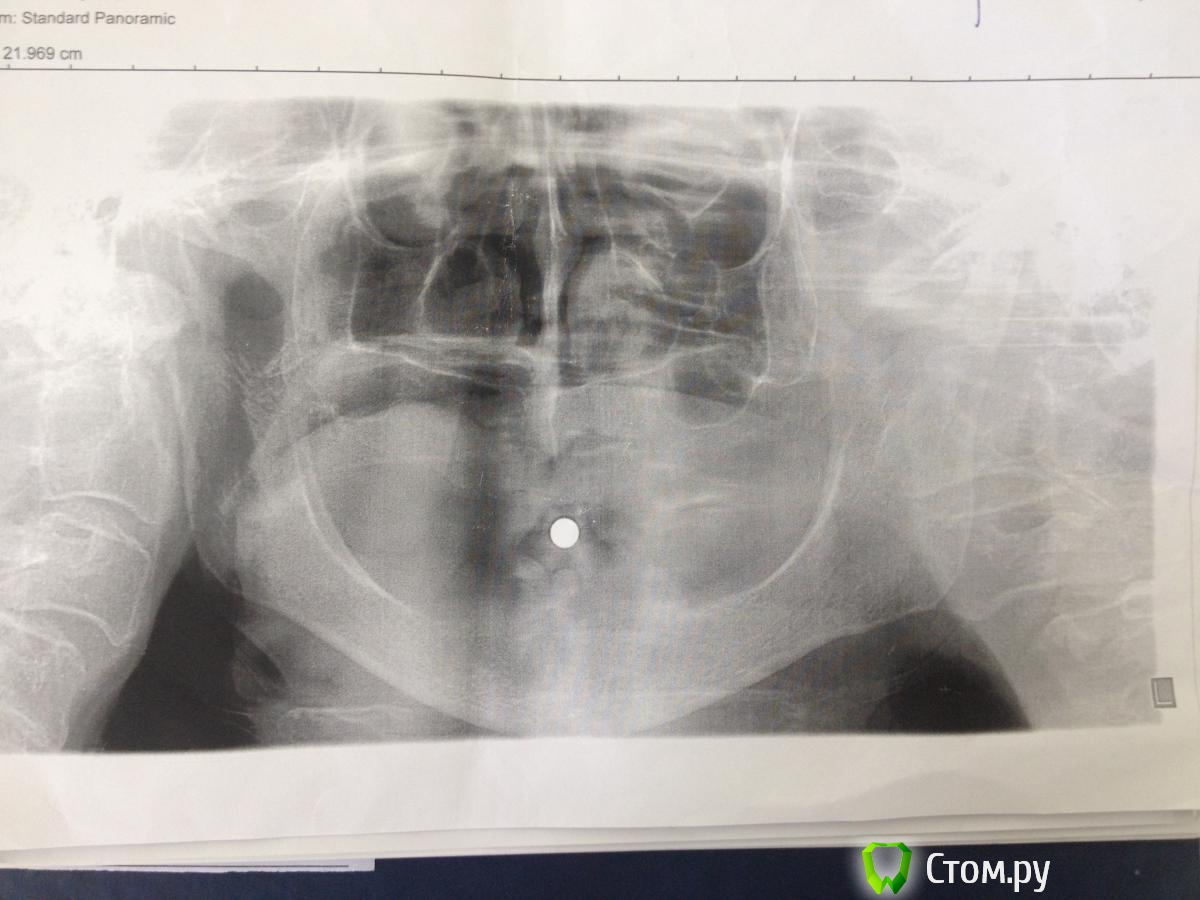

MaxDok Опубликовано 27 июня, 2014 Поделиться Опубликовано 27 июня, 2014 Всем добрый день !Пациенту 72 года. Интересует н.ч.,планируется установка 4 имплантов для фиксации съемного протеза . Кто каким путем пошел бы в данной ситуации ? Что можете посоветовать по оптг , ширина кости 2-3 мм . Ссылка на комментарий

kriokov Опубликовано 27 июня, 2014 Поделиться Опубликовано 27 июня, 2014 Всем добрый день !Пациенту 72 года. Интересует н.ч.,планируется установка 4 имплантов для фиксации съемного протеза . Кто каким путем пошел бы в данной ситуации ? Что можете посоветовать по оптг , ширина кости 2-3 мм . пусть хирурги повнимательней подбородок посмотрят от 44 до 34, там толщины кости обычно хватает.Свод сформировать можно во фронте тоже .Локаторы, самое простое. Ссылка на комментарий

red_butler Опубликовано 27 июня, 2014 Поделиться Опубликовано 27 июня, 2014 Часто проще со шлифовать до необходимой ширины, сделайте кт 4 Ссылка на комментарий

MaxDok Опубликовано 28 июня, 2014 Автор Поделиться Опубликовано 28 июня, 2014 (изменено) пусть хирурги повнимательней подбородок посмотрят от 44 до 34, там толщины кости обычно хватает. Свод сформировать можно во фронте тоже . Локаторы, самое простое.Спасибо ,хирург говорит там вообще не куда , миники только во фронте не будут нормально работать ИМХО , но я передам ))Свод Вы имеете вестибулопластику сделать ? Да локаторы попроще , но учитывая атрофию , думаю нужно что то "пожещще" в плане фиксации Изменено 28 июня, 2014 пользователем MaxDok Ссылка на комментарий

MaxDok Опубликовано 28 июня, 2014 Автор Поделиться Опубликовано 28 июня, 2014 Часто проще со шлифовать до необходимой ширины, сделайте ктТак иногда делали , но тут видимо некуда уже сошлифовывать , природа постаралась за нас Хотя это мое дилетантское мнение . На кт отправим объязательно. Ссылка на комментарий